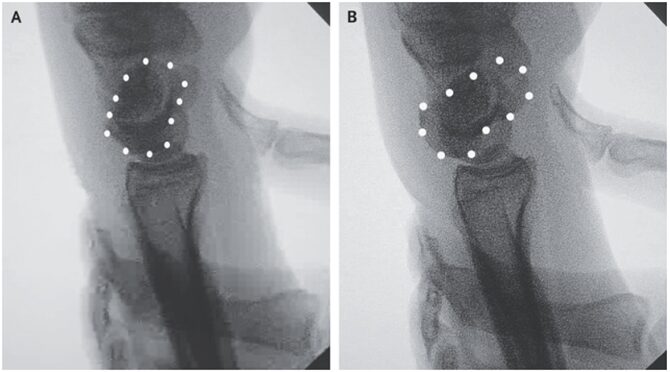

麻酔下に舟状骨移動テストが施行され、手首が尺骨から橈骨方向に移動したとき舟状骨に対する掌側の圧力により舟状骨の背側亜脱臼が確認された(A、B)。